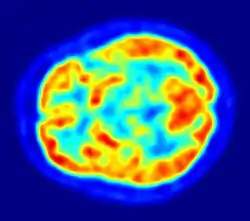

PET imaging with FDG takes advantage of the fact that the brain is normally a rapid user of glucose. Standard FDG PET of the brain measures regional glucose use and can be used in neuropathological diagnosis.

Brain pathologies such as Alzheimer's disease (AD) greatly decrease brain metabolism of both glucose and oxygen in tandem. Therefore FDG PET of the brain may also be used to successfully differentiate Alzheimer's disease from other dementing processes, and also to make early diagnoses of Alzheimer's disease. The advantage of FDG PET for these uses is its much wider availability. Some fluorine-18 based radioactive tracers used for Alzheimer's include florbetapir, flutemetamol, Pittsburgh compound B (PiB) and florbetaben, which are all used to detect amyloid-beta plaques, a potential biomarker for Alzheimer's in the brain.[17]